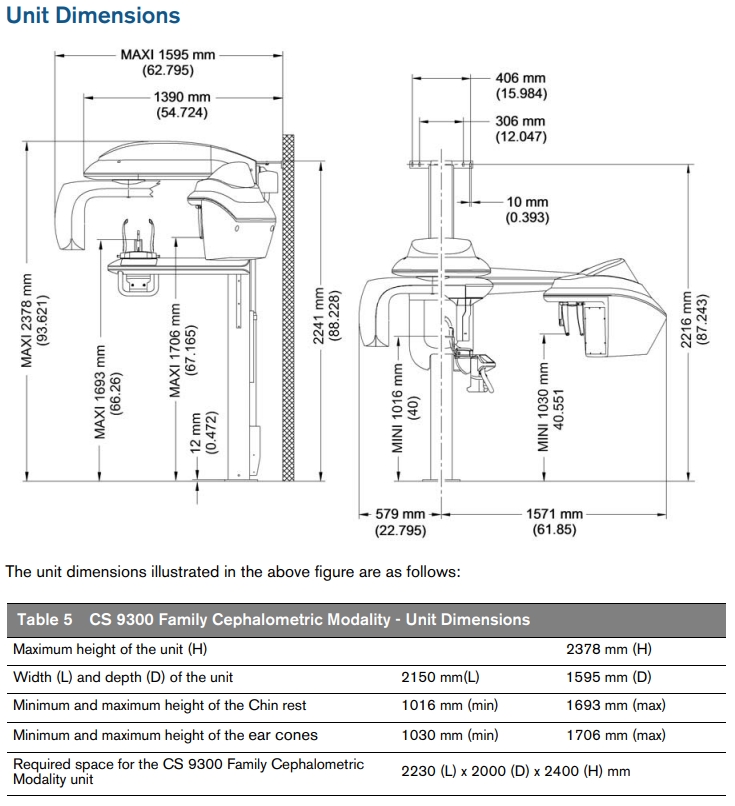

Carestream Kodak 9300c Select Panoramic, Cephalometric, Cone Beam

Carestream Kodak 9300c Select Pan/Ceph, Cone Beam

Imagine you could perform all of your exams with one system. With the CS 9300 family, that dream is now a reality. Featuring dual-modality panoramic and 3D imaging with exceptional detail and range, the CS 9300 is the perfect all-in-one solution for your practice. And, with up to seven selectable fields of view, Low Dose modes, and an optional cephalometric module, the unit is a versatile solution for any practice.